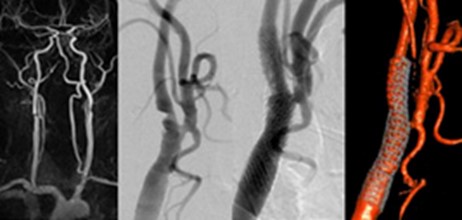

Schonende Behandlung von Stenosen der Hals- und Hirnarterien

Engstellen der Halsschlagadern – am häufigsten ist dabei die extrakranielle Carotisstenose – sind häufig. Zumeist treten sie im Laufe des Älterwerdens auf. Jedoch auch jüngere Menschen können beispielsweise infolge von Verletzungen der Halsgefäße oder eines unbemerkten arteriellen Bluthochdruckes betroffen sein. Derartige Engstellen fallen oft im Rahmen von Routineuntersuchungen beim Hausarzt oder Neurologen/Kardiologen auf oder wenn sie zu Beschwerden führen: kurzzeitige fokal-neurologische Symptome von wenigen Sekunden/Minuten Dauer oder manifeste Schlaganfälle mit vorübergehenden oder bleibenden Ausfallerscheinungen. Bei asymptomatischen, gering- bis mittelgradigen Engstellen genügt häufig eine medikamentöse Behandlung mit Blutverdünnern in Verbindung mit der Reduktion von Risikofaktoren. Bei progredienten oder höhergradigen oder symptomatischen Stenosen kann allerdings eine zügige Behandlung erforderlich werden.

Neben der „offenen“ Operation hat sich die Behandlung über den Katheter als gleichwertige, aber deutlich schonendere Behandlungsmethode etabliert. Dabei wird von der Leiste aus ein dünner Katheter kurz vor der Engstelle positioniert und die Engstelle mit einem dünnen ultraweichen Mikrodraht sondiert. Im Anschluss erfolgt über den einliegenden Mikrodraht die Platzierung einer selbstexpandierbaren Gefäßstütze (eines sog. Stents), die die Engstelle schonend aufdehnt. Abhängig von der Beschaffenheit der Stenose ist manchmal der Einsatz eines kleinen Ballons nötig, mit dem die Engstelle vorgedehnt und/oder nachgedehnt wird. Dieser Eingriff, der ca. 30-45 Minuten dauert, findet in der Regel bei wacher Patientin oder wachem Patienten statt, da er nicht schmerzhaft ist.